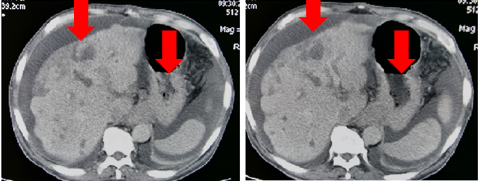

发病后CT(外院2017.11):贲门胃底部溃疡性肿物考虑恶性,腹腔多发肿大淋巴结,考虑转移。

图表1-1:发病后CT(外院2017.11)

CT(外院2018.05):肝内多发占位,考虑转移;贲门胃底部溃疡性肿物;胃低及胃左动脉多发肿大淋巴结;考虑转移。

图表1-2:CT(外院2018.05)